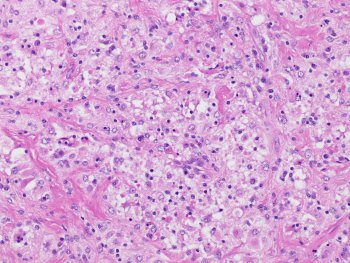

A 60 year-old male presented with multiple skin lesions which was biopsied (figure). Wokup revealed the lesional cells positive for OCT2, CD68, & negative for MelanA/HMB45/SOX10.

This is a case of Rosai-Dorfman Disease (RDD) that are characterized by enlarged round to oval nuclei, pale chromatin, conspicuous nucleoli, and abundant pale eosinophilic cytoplasm. By immunohistochemistry, the RDD cells are positive for histiocytic markers (CD68, CD163), S100, and OCT2. Approximately 50% of these RDD cases harbor MAPK pathway gene mutations, most common being KRAS, NRAS and MAP2K1 (PMID: 37167084).